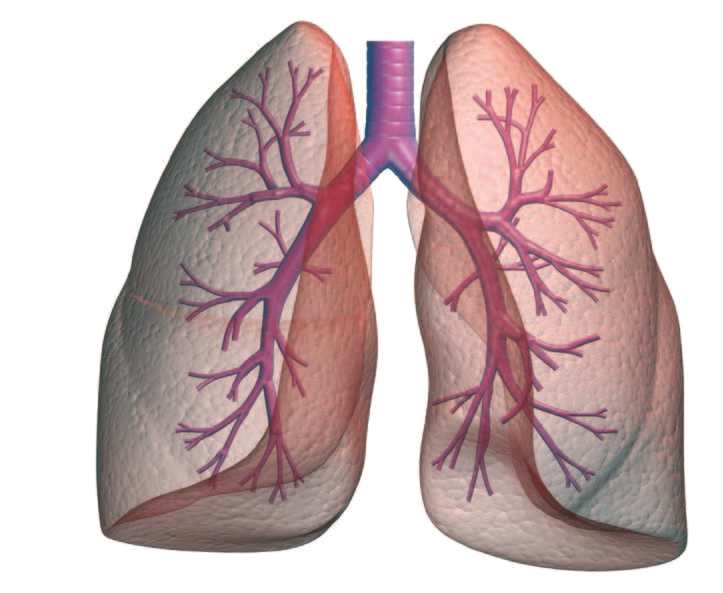

-%D9%88%D8%B5%D9%88%D8%B1%D8%A9-%D8%AB%D9%84%D8%A7%D8%AB%D9%8A%D8%A9-%D8%A7%D9%84%D8%A3%D8%A8%D8%B9%D8%A7%D8%AF-%D9%84%D9%84%D8%B1%D8%A6%D8%AA%D9%8A%D9%86-%D9%88%D8%A7%D9%84%D9%82%D8%B5%D8%A8%D8%A9-%D8%A7%D9%84%D9%87%D9%88%D8%A7%D8%A6%D9%8A%D8%A9.jpg)

جهاز تنفسي ويكيبيديا

وظائف الرئتين الرئة البشرية البنية الوظيفة الدواء 2020

أين تقع الرئتين في جسم الإنسان موضوع